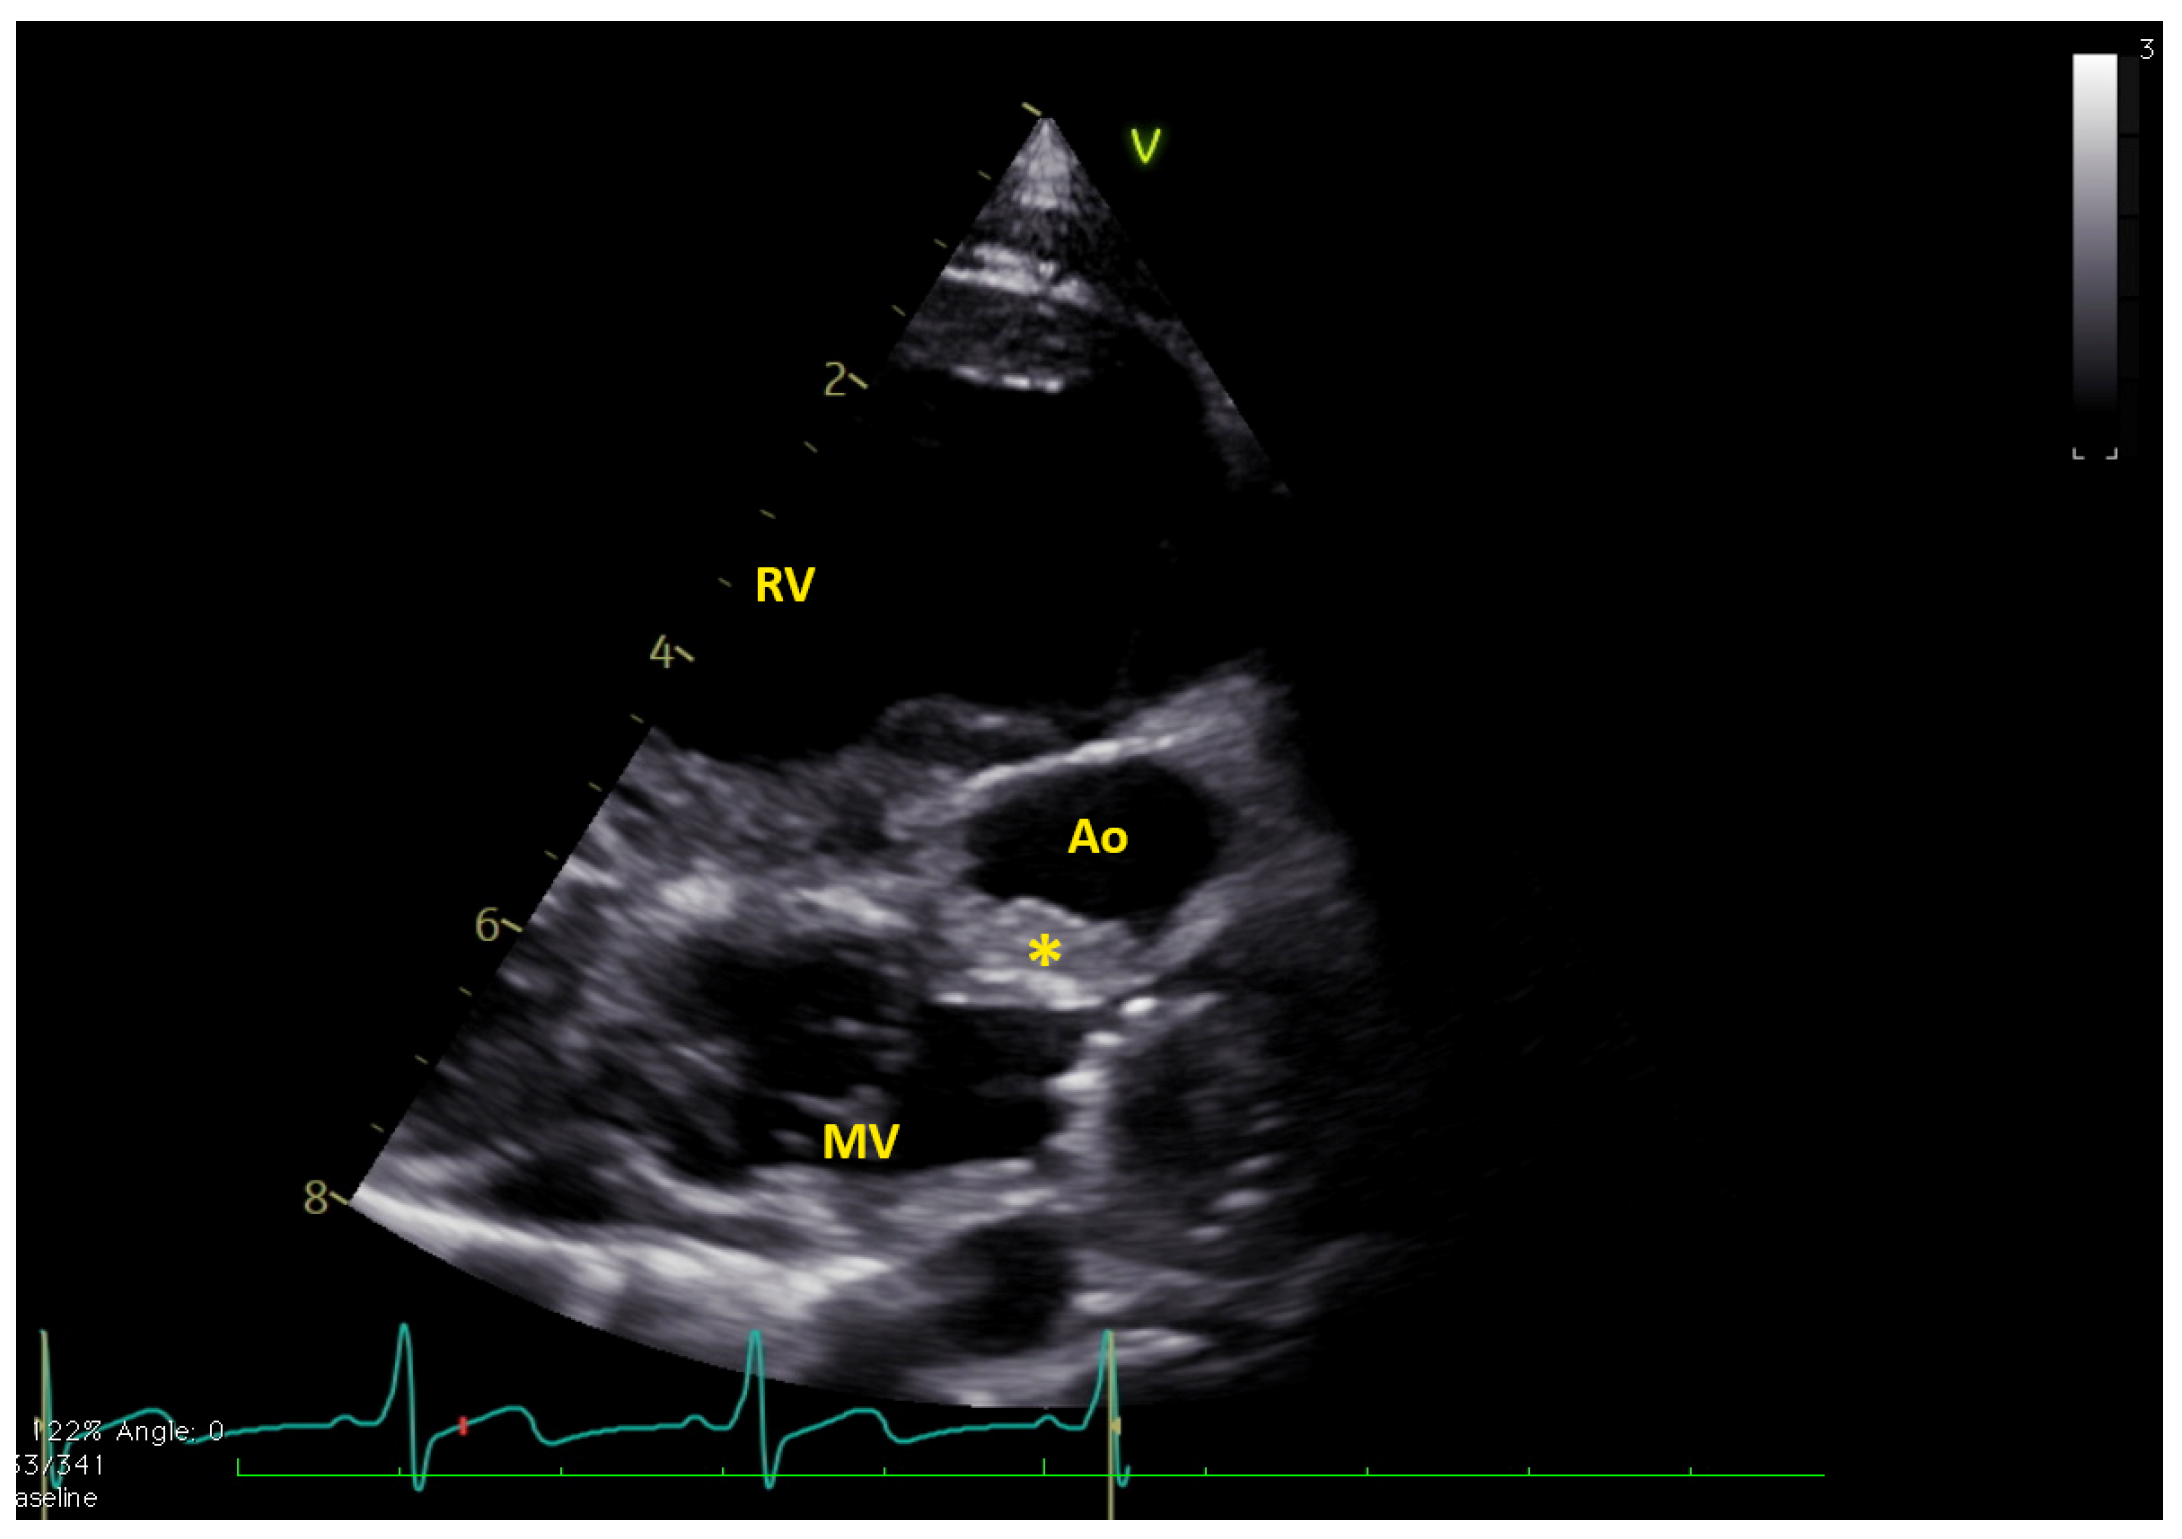

Figure 1.

Long axis view showing the thrombus (*) in native aorta (Ao). MV = mitral valve; RV = right ventricle. The native aorta was tricuspid, with moderately hypoplastic annulus (e.g., 7.8 mm, z-score −5.2), while the aortic root was only mildly hypoplastic (13.4 mm, z-score −2.5) (Video S1).